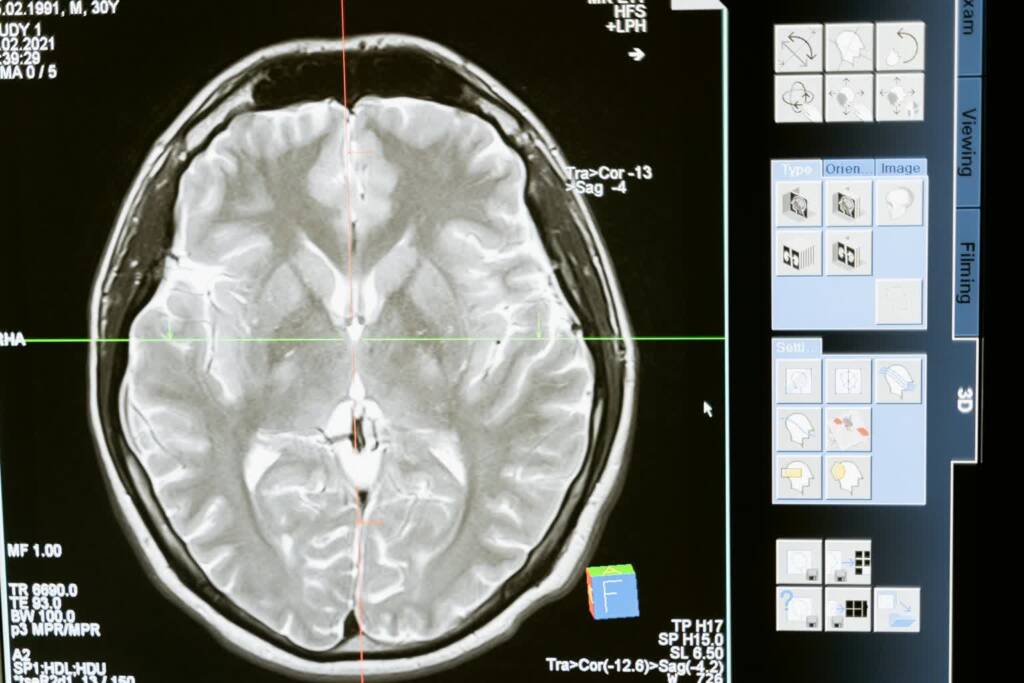

Po 57. roku życia mózg staje się bardziej podatny na chorobę Alzheimera i nowotwory mózgu – to najnowsze badania naukowców z Madrytu.